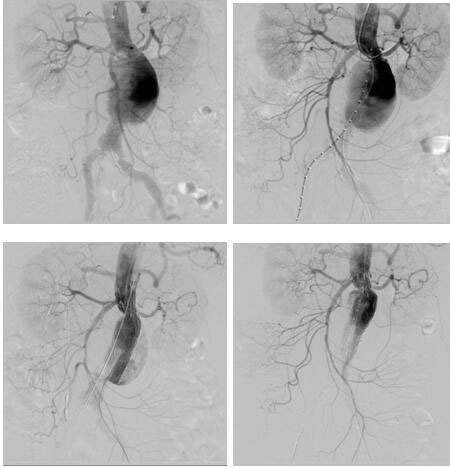

血管介入科完成我院首例腎下復(fù)雜型腹主動脈瘤腔內(nèi)修復(fù)

日前,血管介入科為一位患腎下復(fù)雜型腹主動脈瘤(左腎動脈距離瘤體僅4mm)74歲老年女性完成腎動脈煙囪+腹主動脈瘤覆膜支架腔內(nèi)隔絕術(shù),術(shù)后恢復(fù)良好。該患者基礎(chǔ)疾病多,已經(jīng)出現(xiàn)腹痛癥狀,腹主動脈瘤瘤體隨時有破裂風(fēng)險,但左腎動脈距離瘤體僅4mm,采取傳統(tǒng)開放手術(shù)(腹主動脈瘤切除+Y型人工血管置換+左腎動脈轉(zhuǎn)流術(shù))手術(shù)創(chuàng)傷大,手術(shù)風(fēng)險高,經(jīng)血管外科治療團(tuán)隊(duì)反復(fù)研究病例,并在院領(lǐng)導(dǎo)支持下,決定采取腔內(nèi)治療:先經(jīng)肱動脈穿刺置鞘于左腎動脈留置導(dǎo)絲,再經(jīng)雙側(cè)股動脈上導(dǎo)絲導(dǎo)管造影定位,在施放腹主動脈主體支架前先經(jīng)左肱動脈留置導(dǎo)絲導(dǎo)引下于左腎動脈置入VIABAHN支架保證左腎動脈供血,再釋放腹主動脈主體支架,解決了左腎動脈距離瘤體過近的問題。該例手術(shù)的完成,標(biāo)志著我院在腹主動脈瘤的腔內(nèi)治療跨入省內(nèi)領(lǐng)先行列。